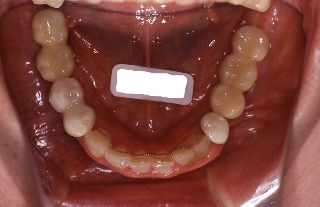

インプラント治療の為の矯正治療症例1

初診時年齢58歳。下顎臼歯部インプラント治療前の咬合改善を目的に来院。

咬み合わせを高くする事で受け口の改善ならびに下顎インプラント挿入スペースを作成した。

矯正治療と並行して専門医によるインプラント治療を行った。

下顎 下顎 下顎